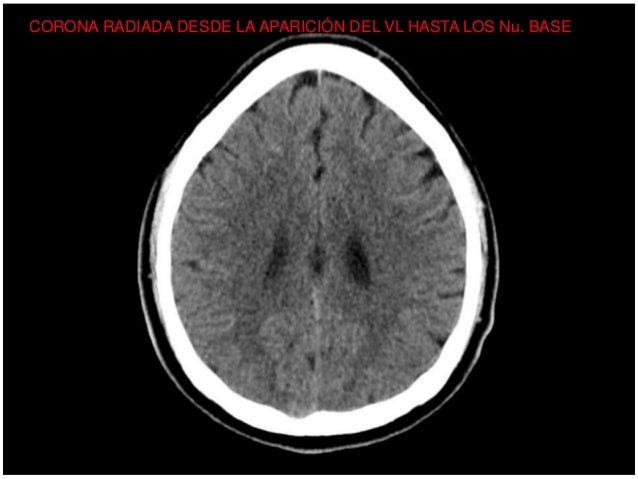

Lectura Sistematica Del Tc De Craneo